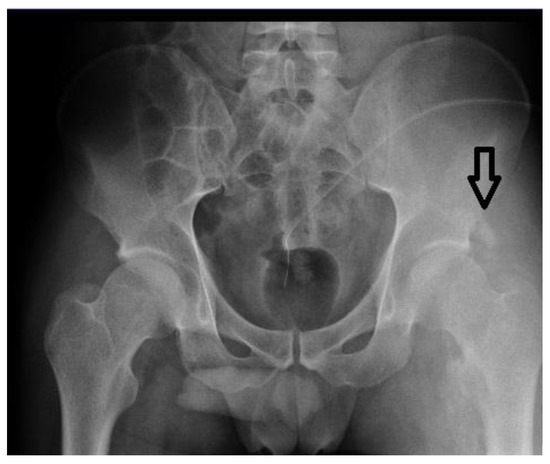

| 4 | 30 | 63 months | C5 | Paresis of upper limbs, paraplegia | Spastic (MAS 3/4) | 2900 | Fracture |